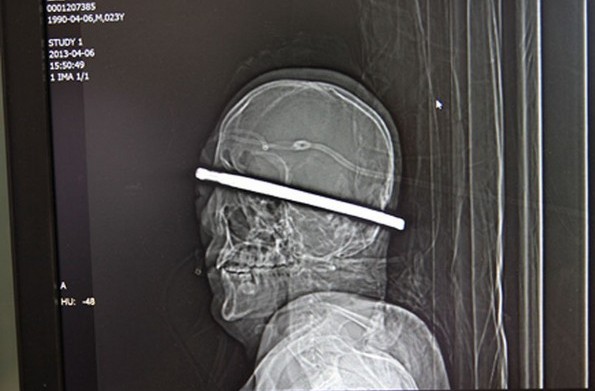

另一起发生在中国的事故,这名工人被一根钢筋从后脑勺刺入,从前面右眼的一角穿出。它被紧急送往当地医院,医生们不得不求助消防队来剪短这根钢筋